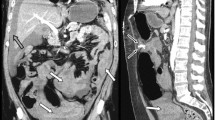

Sappey’s superior artery (SSA): an artery traversing the cranial portion of the falciform or coronary ligaments (Fig. 1). It may connect the intrahepatic artery around the falciform ligament-attaching area with an artery of the diaphragm (a branch of any inferior phrenic artery) or the body wall (a branch of any internal mammary artery). It may terminate at any point during its course as seen on C-arm CTHA. The flow direction relative to the liver can be either hepatofugal or hepatopetal. If multiple arteries satisfied the definition above, the most dominant one in diameter and length was regarded as the SSA and was then categorised by the following grades: 0 = not present; 1 = suspicious; 2 = intermediate; or 3 = prominent. The SSA was considered radiologically conspicuous if the grade was 2 or higher.

Fig. 1 A 71-year old male patient underwent C-arm CT hepatic arteriography (CTHA) before a chemoembolization procedure. (a) A Sappey’s superior artery (SSA; arrowhead) originated from the surface of the left hepatic lobe and distributed to the costal origin of the left diaphragm via the cranial portion of the falciform ligament and the anterior abdominal fat body which appeared as intraperitoneal fat space on this CT image. (b) The artery was seen merely as a vague linear structure (arrowhead) on the multidetector row CT image